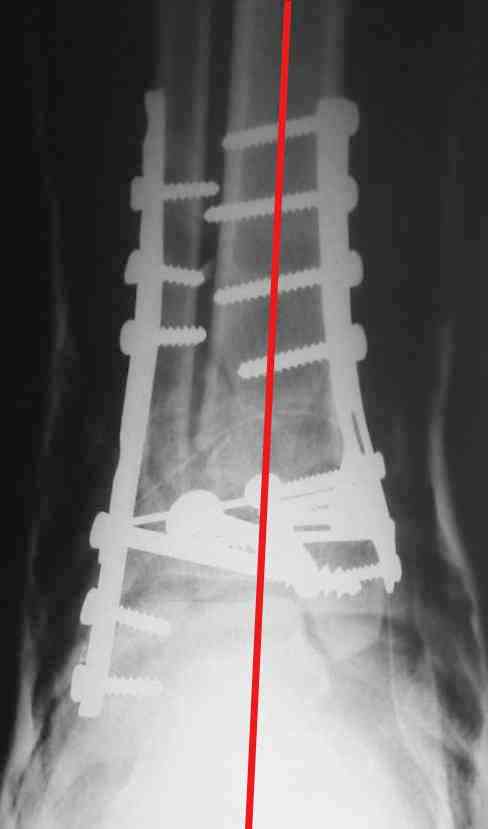

На представленном снимке видно, что эпифиз смещен латерально.

Сейчас с этим ничего не сделать, похоже.

Однозначно сказать сложно.Расстояние между тараном и медиальной лодыжкой меньше чем между тараном и крышей большеберцовой кости.Это может быть за счёт не правильной укладки.Пока не отчаиваетесь.Главное вы поняли принцип.Сделайте несколько проекций прямых и посмотрим.Для всех интересно.С уважением